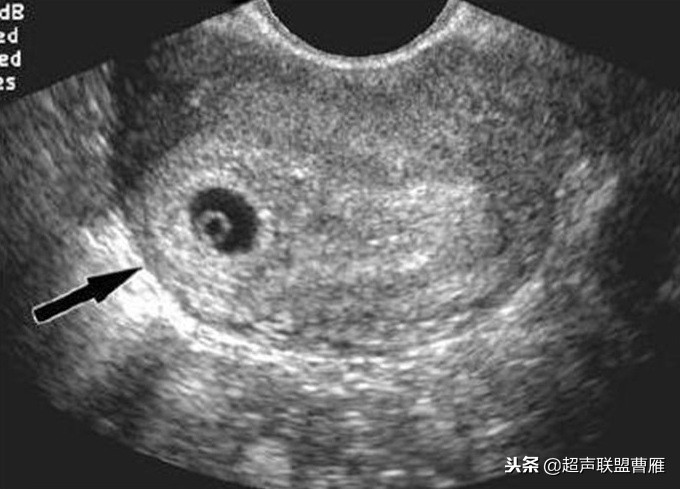

妊娠37天超声检查卵黄囊可以显示,羊膜腔及胚胎不能显示

真实的卵黄囊、胚体及羊膜腔形象

妊娠37天出现卵黄囊

在妊娠妊娠38天前后(36-40)天可以见到卵黄囊。 孕囊在6-9mm的可以见到其中有卵黄囊。